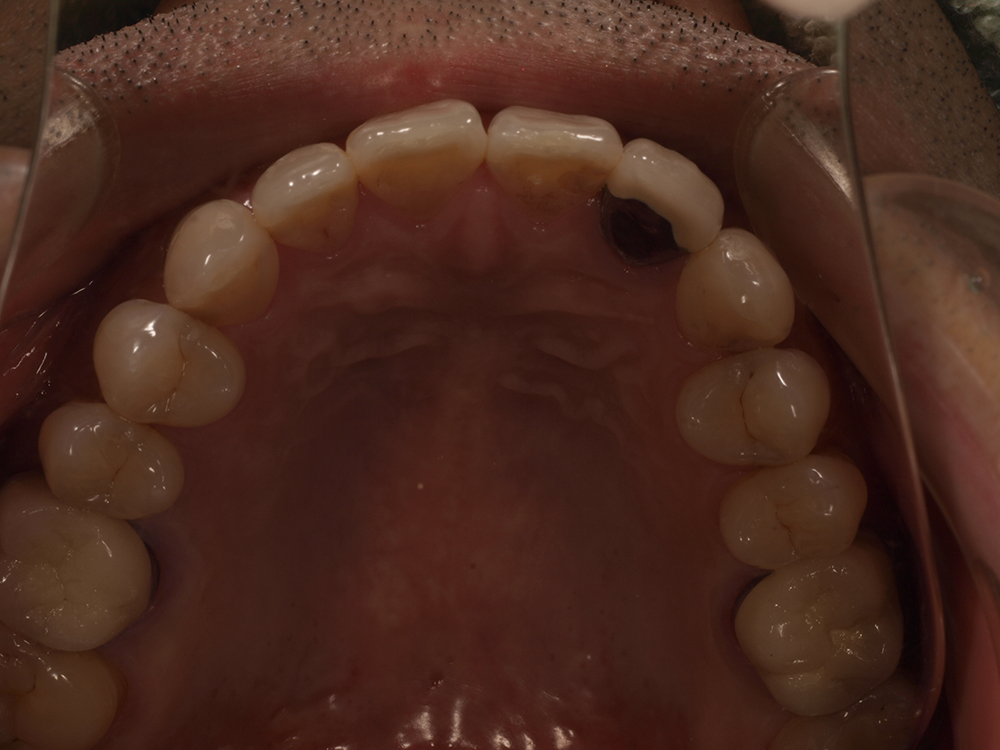

53歳 男性

- 主訴

- 全然噛めない。上の歯が取れてきた

- 処置内容

- 上顎:8本 下顎:2本

- 治療費用

- 上顎:約320万円(税込)、下顎:約160万円(税込)

- 治療期間

-

上顎:1年(仮歯まで8か月)

下顎:8か月(仮歯まで5か月)

- リスク

- 上部構造物、仮歯の破折、術後の腫れ(3日)、人工歯根脱落リスクがあります